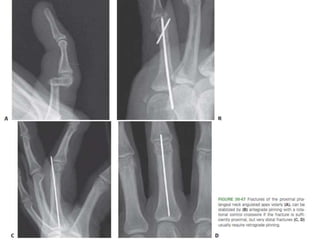

• #80 Fractures of the proximal phalangeal neck angulated apex volarly (A), can be stabilized by (B) antegrade pinning with a rotational control crosswire if the fracture is sufficiently proximal, but very distal fractures (C, D) usually require retrograde pinning.

• #81 Transverse shaft fractures of P1 are best stabilized by 0.045-inch K-wires passed longitudinally through the metacarpal head and removed at 3 weeks.